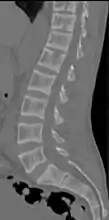

CT scan of the same case.[13]